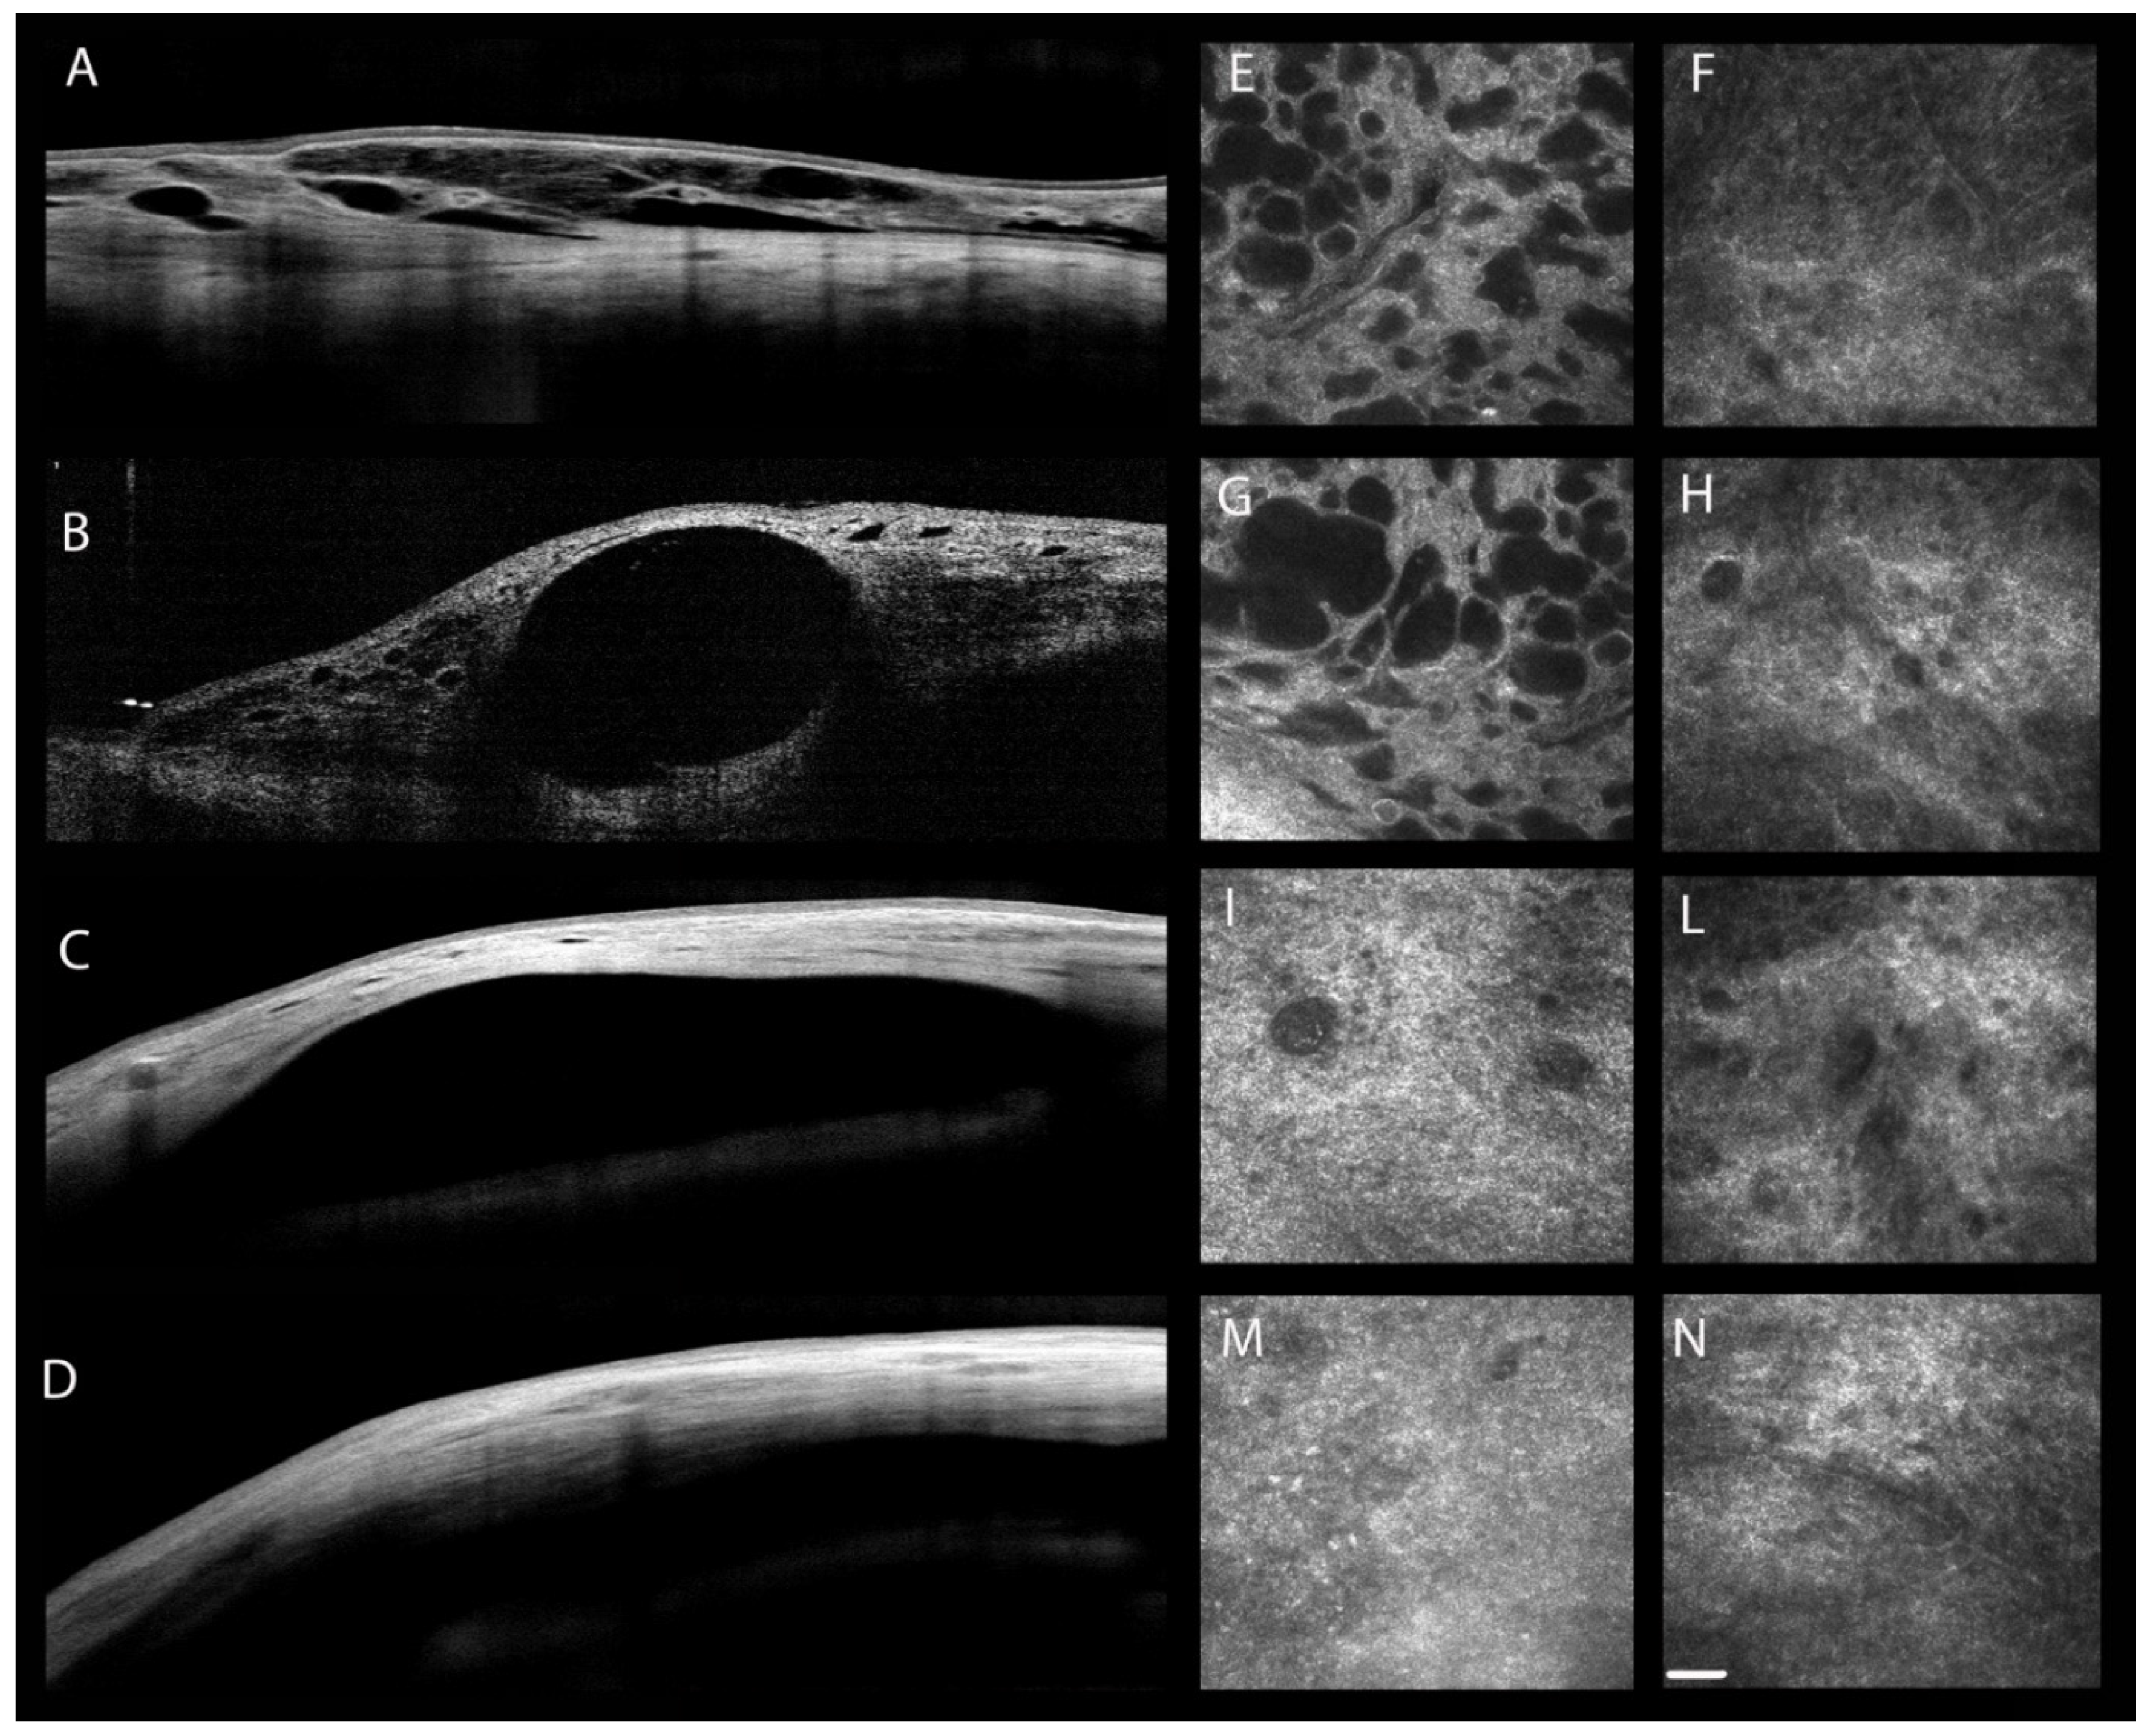

| Ciancaglini M. et al. [88] | 2008 | IVCM a AS-OCT j | POAG e PXG f | Trabeculectomy | |

- Ciancaglini, M.; Carpineto, P.; Agnifili, L.; Nubile, M.; Lanzini, M.; Fasanella, V.; Mastropasqua, L. Filtering bleb functionality: A clinical, anterior segment optical coherence tomography and in vivo confocal microscopy study. J. Glaucoma 2008, 17, 308–317. [Google Scholar] [CrossRef]

- Sacchi, M.; Agnifili, L.; Brescia, L.; Oddone, F.; Villani, E.; Nucci, P.; Mastropasqua, L. Structural imaging of conjunctival filtering blebs in XEN gel implantation and trabeculectomy: A confocal and anterior segment optical coherence tomography study. Graefes Arch. Clin. Exp. Ophthalmol. 2020, 258, 1763–1770. [Google Scholar] [CrossRef]